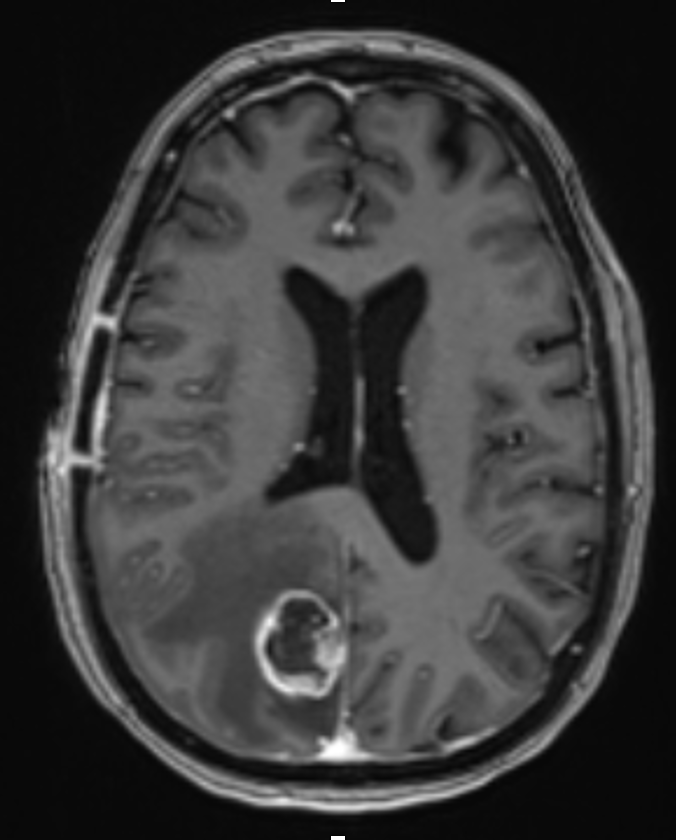

I'm Dr. David Wasilewski, a senior neurosurgery resident (PGY-6) at University Hospital Düsseldorf, with prior training at Charité – Universitätsmedizin Berlin and a research fellowship at CNIO Madrid. My clinical and scientific focus lies in glioblastoma, lower-grade gliomas, brain metastases, and general neurosurgery. I’ve contributed to multiple peer-reviewed publications (H-index 9), co-supervised doctoral theses, and led or co-led translational research projects in neuro-oncology across Europe. Furthermore I am interested in patient education and conveying information from the neurooncology community to a broader public. This site shares selected educational resources for patients/relatives and also doctors in terms of specific topics in neurooncology and neurooncology practice.